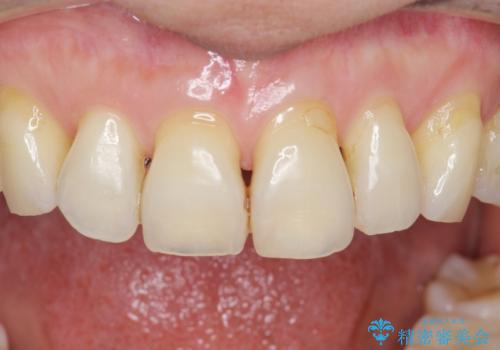

- 歯ぎしりが気になる 歯が将来ダメになるのが怖いとの事で相談を受けた患者様です。

型取り(上下)をして自費のナイトガードを作製しました。